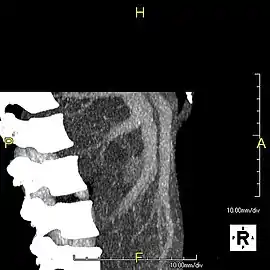

- Axial CT image showing anomalous hepatic veins coursing on the liver's subcapsular anterior surface[70]

- Maximum intensity projection (MIP) CT image as viewed anteriorly showing the anomalous hepatic veins coursing on the anterior surface of the liver

- Lateral MIP view in the same patient as previous image

- A CT scan in which the liver and portal vein are shown